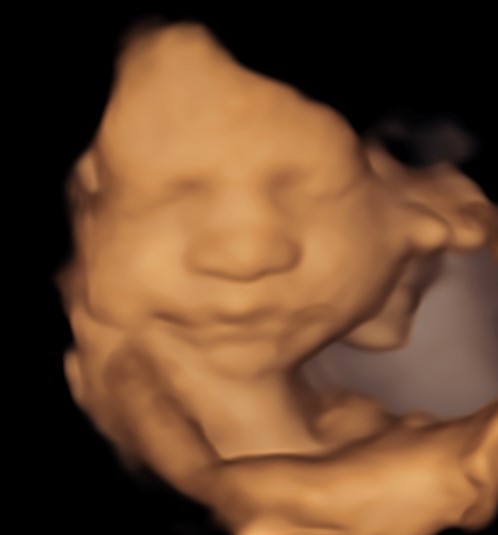

4D/5D/HD Ultrasound Gallery

Gallery